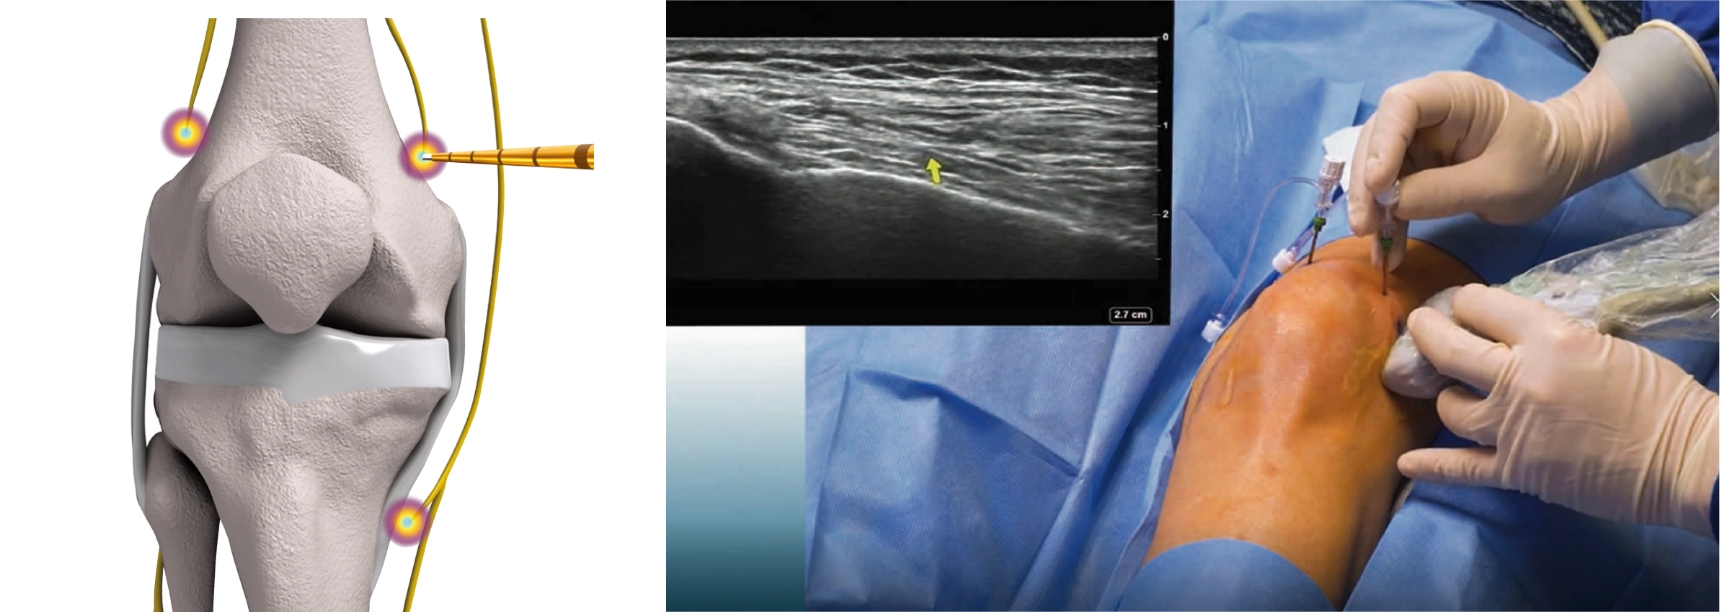

ターゲットとする神経

Coolief* 疼痛管理用高周波システムは、超音波エコー下で左図の3 つの膝神経をターゲットに、変形性膝関節症に伴う疼痛治療を行います。診断用神経ブロックも同様のターゲットに対して行います。